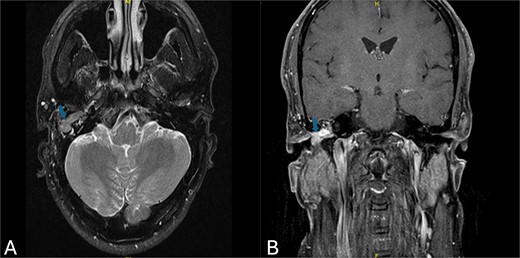

A CT scan of the temporal bones revealed a lesion suggestive of recurrent cholesteatoma (Fig. 1). However, evaluation with preoperative MRI demonstrated a hypervascular lesion in the middle ear extending into the EAC and involving the right epitympanum, making recurrent cholesteatoma less likely (Fig. 2).

(A) Axial MRI view demonstrating a homogeneous soft tissue mass with slightly high signal intensity (arrow). (B) Coronal MRI view revealing a hypervascular mass located in the right epitympanum, without evidence of diffusion (arrow).